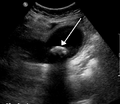

Diagnostic methodBased on symptoms, confirmed by ultrasound[2][4]

Diagnosis is typically confirmed by abdominal ultrasound. Other imaging techniques used are ERCP and MRCP. Gallstone complications may be detected on blood tests.[2]